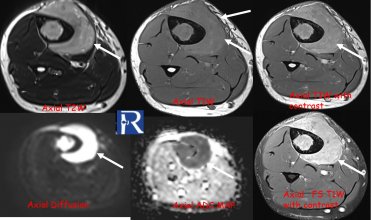

Case Presentation Plantar vein thrombosis (PVT) has traditionally been described as a rare cause of foot pain. However, increasing awareness and mo ...